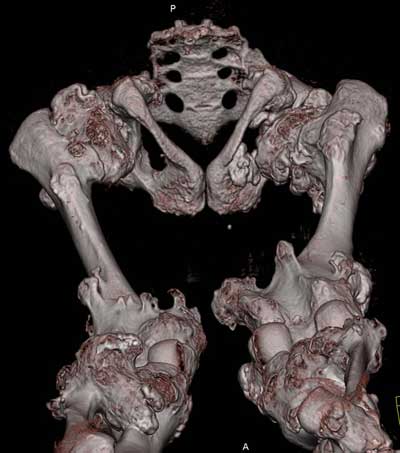

Oбратился больной 30 лет с хондродисплазией, множественными деформациями и экзостозами. Сгибательно-приводящие контрактуры Т/Б сустав, поясничный лордоз.

Интелектуально развит, работает програмистом. Болей нет. Анализы крови в пределах нормы, понижен кальций (общий Ca 1.62, N от 2.3 до 2.75;ионизорованный 0.67, N от 0.7 до 1.07) и щелочная фосфотаза -7.9. По данным КТ, оптическая плотность диафизов 150 - 200 NU (N в его возрасте 300 -350NU) метафизарный остеопороз от 100NU до отрицательных величин - 80 NU.

Больной настоятельно просит об исправлении деформаций и удаления экзостозов области коленных суставов.

30 years old male with chondrodysplasia and multiple exostoses admitted.Multilevel deformities, flexion-adduction limitation of hip ROM, lumbar lordosis. Intellectually developed, working in some software company. Painless. Blood tests are normal, except low Calcium (total serum Ca 1. 62, N is 2.3 - 2.75; ionized 0.67 N is 0.7 -1.07) and low alkaline phosphatase 7.9. Diaphysis bone density is about 150 - 200 NU (N in his age is 300 - 350NU). Metaphis osteoporosis is from 100NU to minus 80 NU.

After Dr Elbatrawy saw the CT scans he added - the case has multible exostosis and the ulna also may need lengthening on both sides; he will need follow up, as one of the multible exostosis may transform to Chondrosarcoma on top of its cartilagenous cap. It is a common problem associated with this condition.